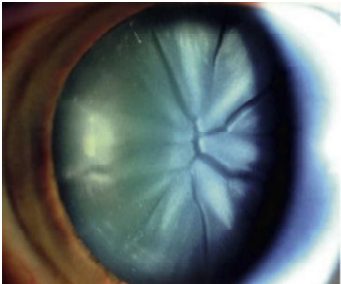

Paciente, 45 anos, chega ao consultório oftalmológico queixando de diminuição na acuidade visual. Ao exame oftalmológico do olho direito, observa-se a seguinte alteração:

Marque a opção que apresenta a pergunta essencial a ser feita ao paciente, considerando a principal causa desse tipo de achado ao exame físico.